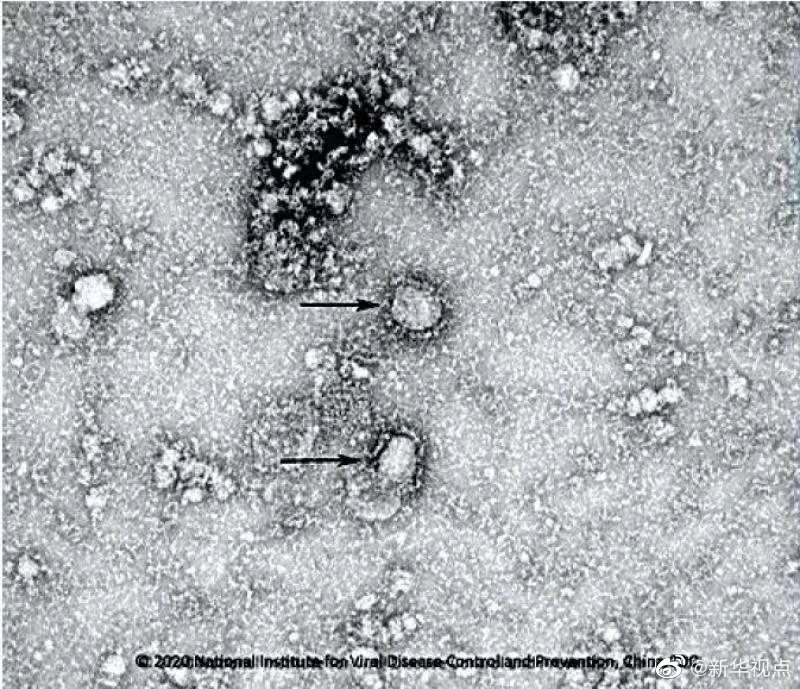

国家病原微生物资源库于2020年1月24日发布了由中国疾病预防控制中心病毒病预防控制所成功分离的我国第一株病毒毒种信息及其电镜照片、新型冠状病毒核酸检测引物和探针序列等国内首次发布的重要权威信息,并提供共享服务。看病毒“真容”↓↓↓(记者田晓航、王秉阳)